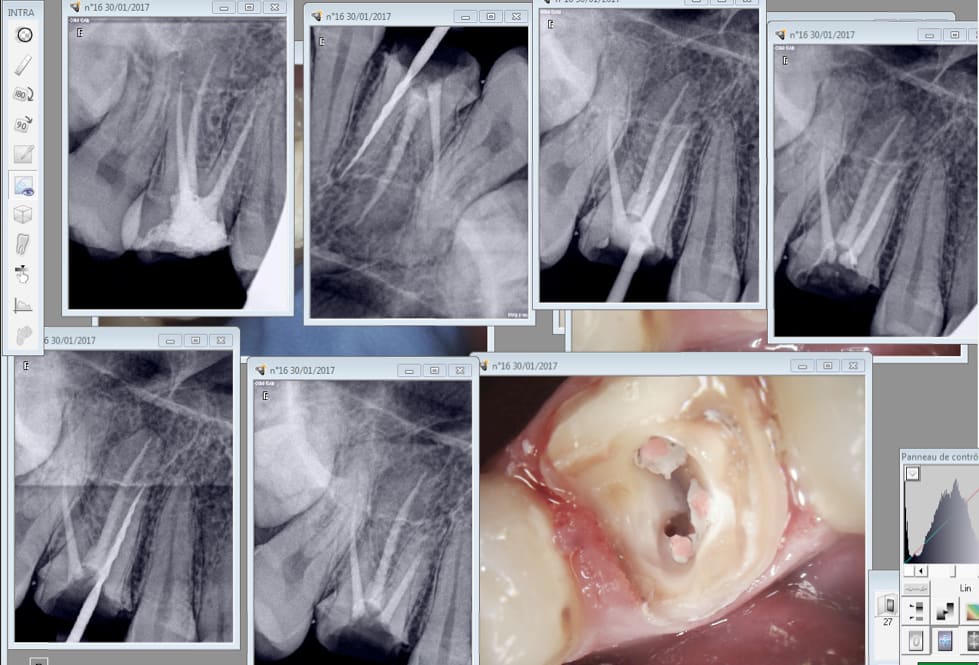

Ca. Endo faite il y a 15 jour. Presque parfaite. Manquait le mV2 fort heureusement en Y avec le MV1.

C'est très bien, mais si le canal MV et MV2 avaient une terminaison commune, qu'est ce qui a conduit le patient à te consulter...et toi a refaire ce travail?

On lui a dit que j'étais pas cher en prothèse ( ca m'a énervé d'ailleurs, je déteste ce genre de raisonnement ) . Et son dentiste lui mettait un rendez vous tous les mois.

Un mv2 non traité ca fout la merde.

Fallait pas la garder vivante au départ. Quand la pulpe est blette elle est blette. Pas une goutte de sang à l'ouverture.

A votre avis en combien de temps j'ai réalisé cette endo ? Toujours pas de cathéthérisme manuel.